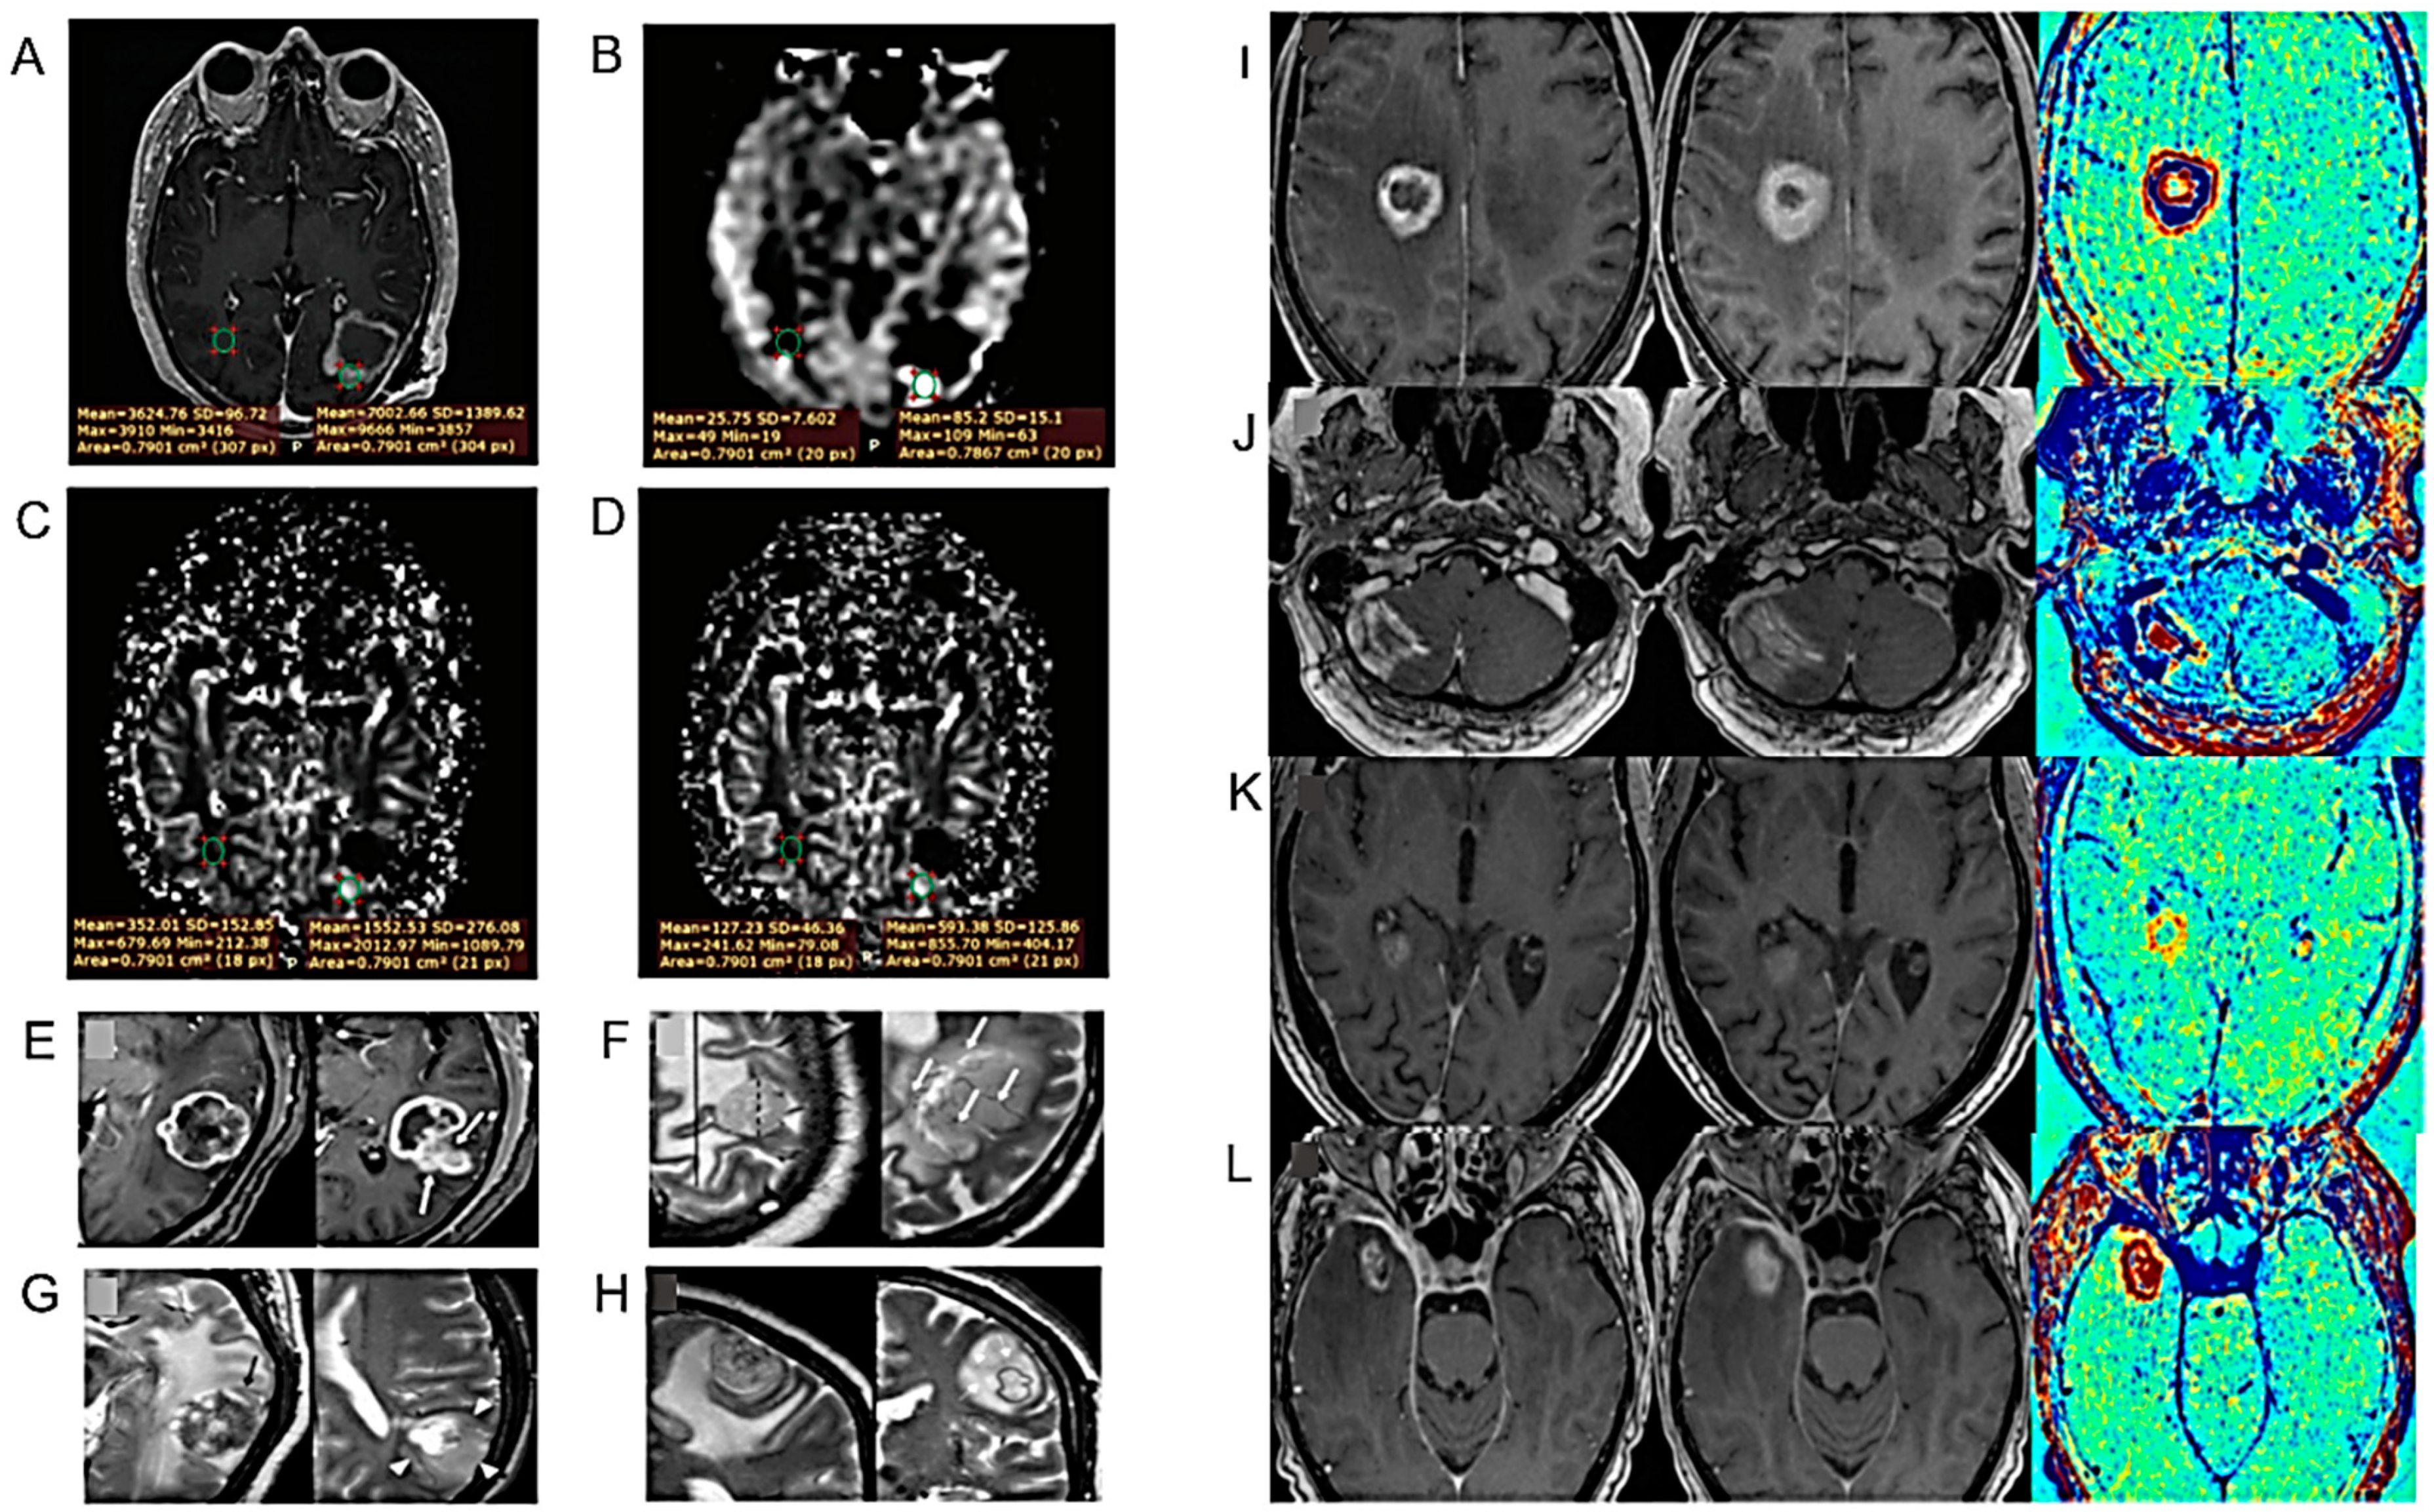

| Study of an analytical qualitative algorithm to differentiate HGG from BM. | 36 patients with histologically proven HGG or solitary BM matched by size and location. | [38] |

| Use of the tissue permeability and microcirculation parameters Ktrans, Kep, IAUC to differentiate PT from TM. | 34 patients with HGG. | [43] |

| Unlike the quantitative measurements of DSC and DCE perfusion maps, their qualitative assessment has low inter-examinator agreement. | HGG patients who underwent re-resection of a new enhancing lesion on post-treatment 3T MR examination including DWI, DCE and DSC sequences. | [45] |

- Voicu, I.P.; Pravatà, E.; Panara, V.; Navarra, R.; Mattei, P.A.; Caulo, M. Differentiating Solitary Brain Metastases from High-Grade Gliomas with MR: Comparing Qualitative Versus Quantitative Diagnostic Strategies. Radiol. Med. 2022, 127, 891–898. [Google Scholar] [CrossRef]

- Dündar, T.T.; Cetinkaya, E.; Yurtsever, İ.; Uysal, Ö.; Aralaşmak, A. Follow-Up of High-Grade Glial Tumor; Differentiation of Posttreatment Enhancement and Tumoral Enhancement by DCE-MR Perfusion. Contrast Media Mol. Imaging 2022, 2022, 6948422. [Google Scholar] [CrossRef] [PubMed]

- Zakhari, N.; Taccone, M.; Torres, C.; Chakraborty, S.; Sinclair, J.; Woulfe, J.; Jansen, G.; Cron, G.; Nguyen, T.B. Qualitative Assessment of Advanced MRI in Post-Treatment High Grade Gliomas Follow Up: Do we Agree? Can. Assoc. Radiol. J. 2022, 73, 187–193. [Google Scholar] [CrossRef] [PubMed]